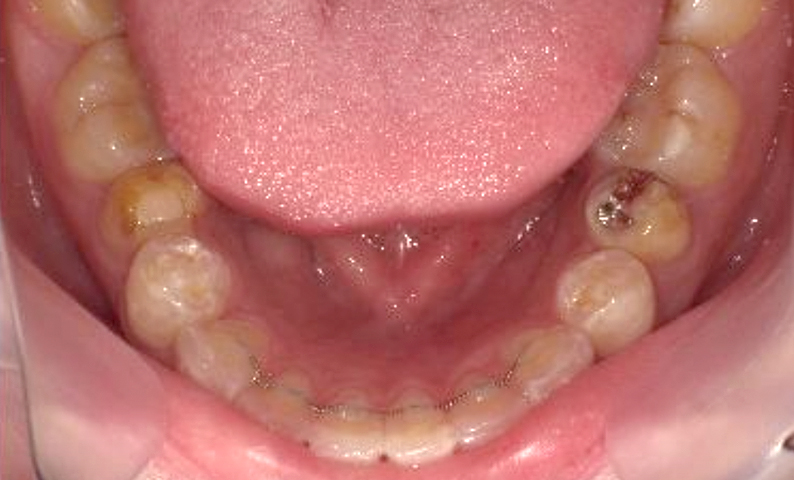

症例_001 下顎だけの部分矯正

治療期間:6ヶ月金額:27万円+税女性前歯のガタガタ下の前歯だけ

| Before | After |

|---|---|

|